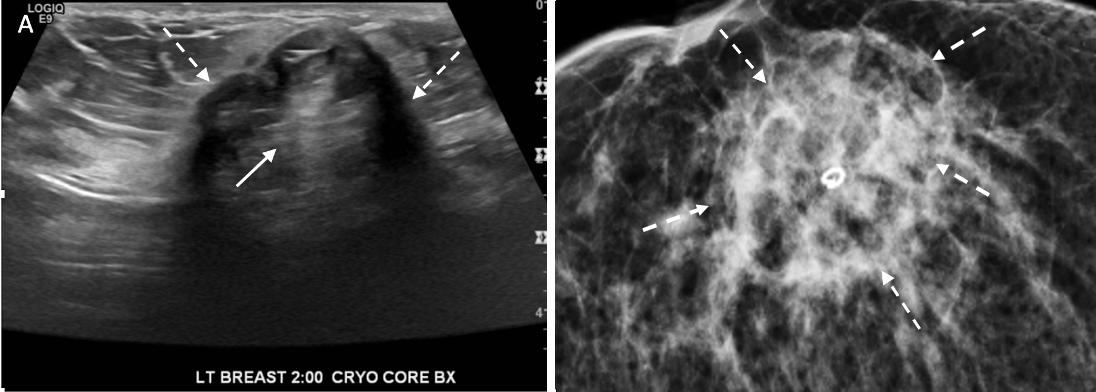

Ultrasound of the breast. Office-based cryoablation is optimized for treatment of ultrasound-visible breast cancers. Consequently, breast ultrasound should be performed of all suspicious imaging abnormalities to assess eligibility for ultrasound-guided cryoablation.

Ultrasound permits assessment of the cancer’s proximity to the overlying skin and underlying chest wall and also enables detection of changes in adjacent tissue architecture (e.g., edema, tissue distortion, extension of tumor into adjacent ducts) and could indicate the presence of more extensive disease that would need to be incorporated into the treatment plan (Image 2).

Image 2. Image A shows dark, dominant, irregular mass encircled by hash marks with intraductal tumor extensions (dark bands bracketed by paired arrows) extending from left and right sides of dominant mass. Image B shows dark, irregular dominant mass (arrow) surrounded by peri-tumoral edema outlined by hash marks